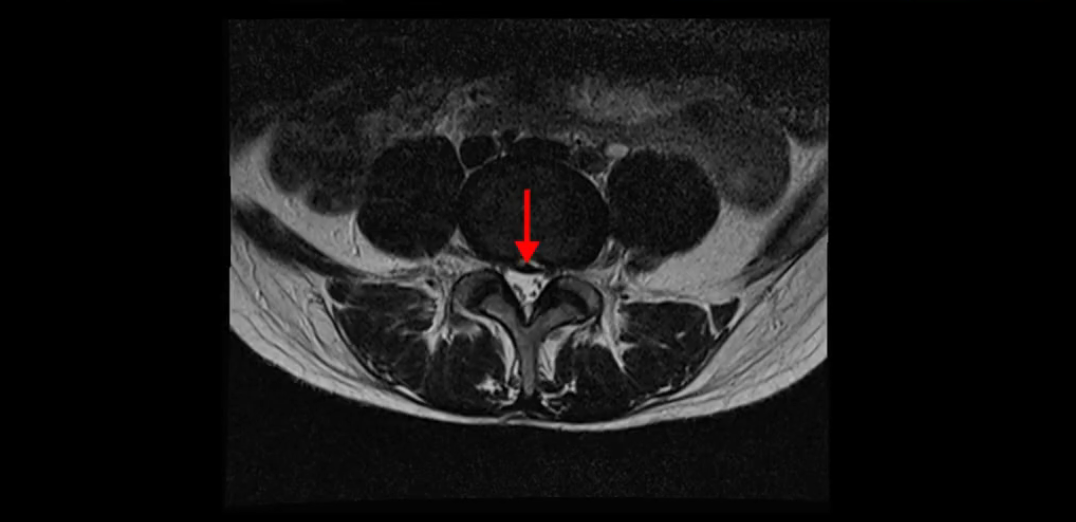

이분 MRI를 보시면 두 마디의 퇴행성디스크가 있습니다. 그리고 디스크가 조금씩 밀려 나와 있고요. 그런데 디스크 탈출 정도는 두 마디 다 심하지 않습니다. 4번 5번에는 디스크 탈출이 약간 있고,

척추관협착도 약간 진행이 되고 있고요.

또한 양쪽 신경 가지가 빠져나가는 추간공은 매우 넓은 상태입니다.

중요한 것은 이 정도 경미한 탈출과 협착으로는 양쪽 다리가 저리고 아플 수가 없습니다.

이분 MRI를 보시면 퇴행성디스크가 있고 약간의 협착이 있지만 이 정도의 퇴행성디스크와 협착으로는 신경이 눌려서 양쪽 다리가 저리고 아픈 증상이 나올 수가 없습니다. 그래서 MRI와 이 환자분의 다리 증상이 매치가 안 된다고 하는 의사들이 많은 겁니다.